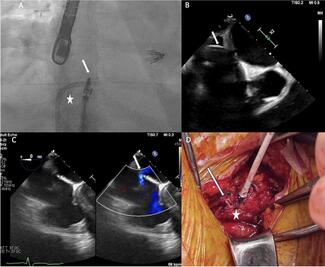

This case demonstrates an issue retrieving a MitraClip into the steerable guide catheter and presents a novel solution to facilitate an exit strategy.